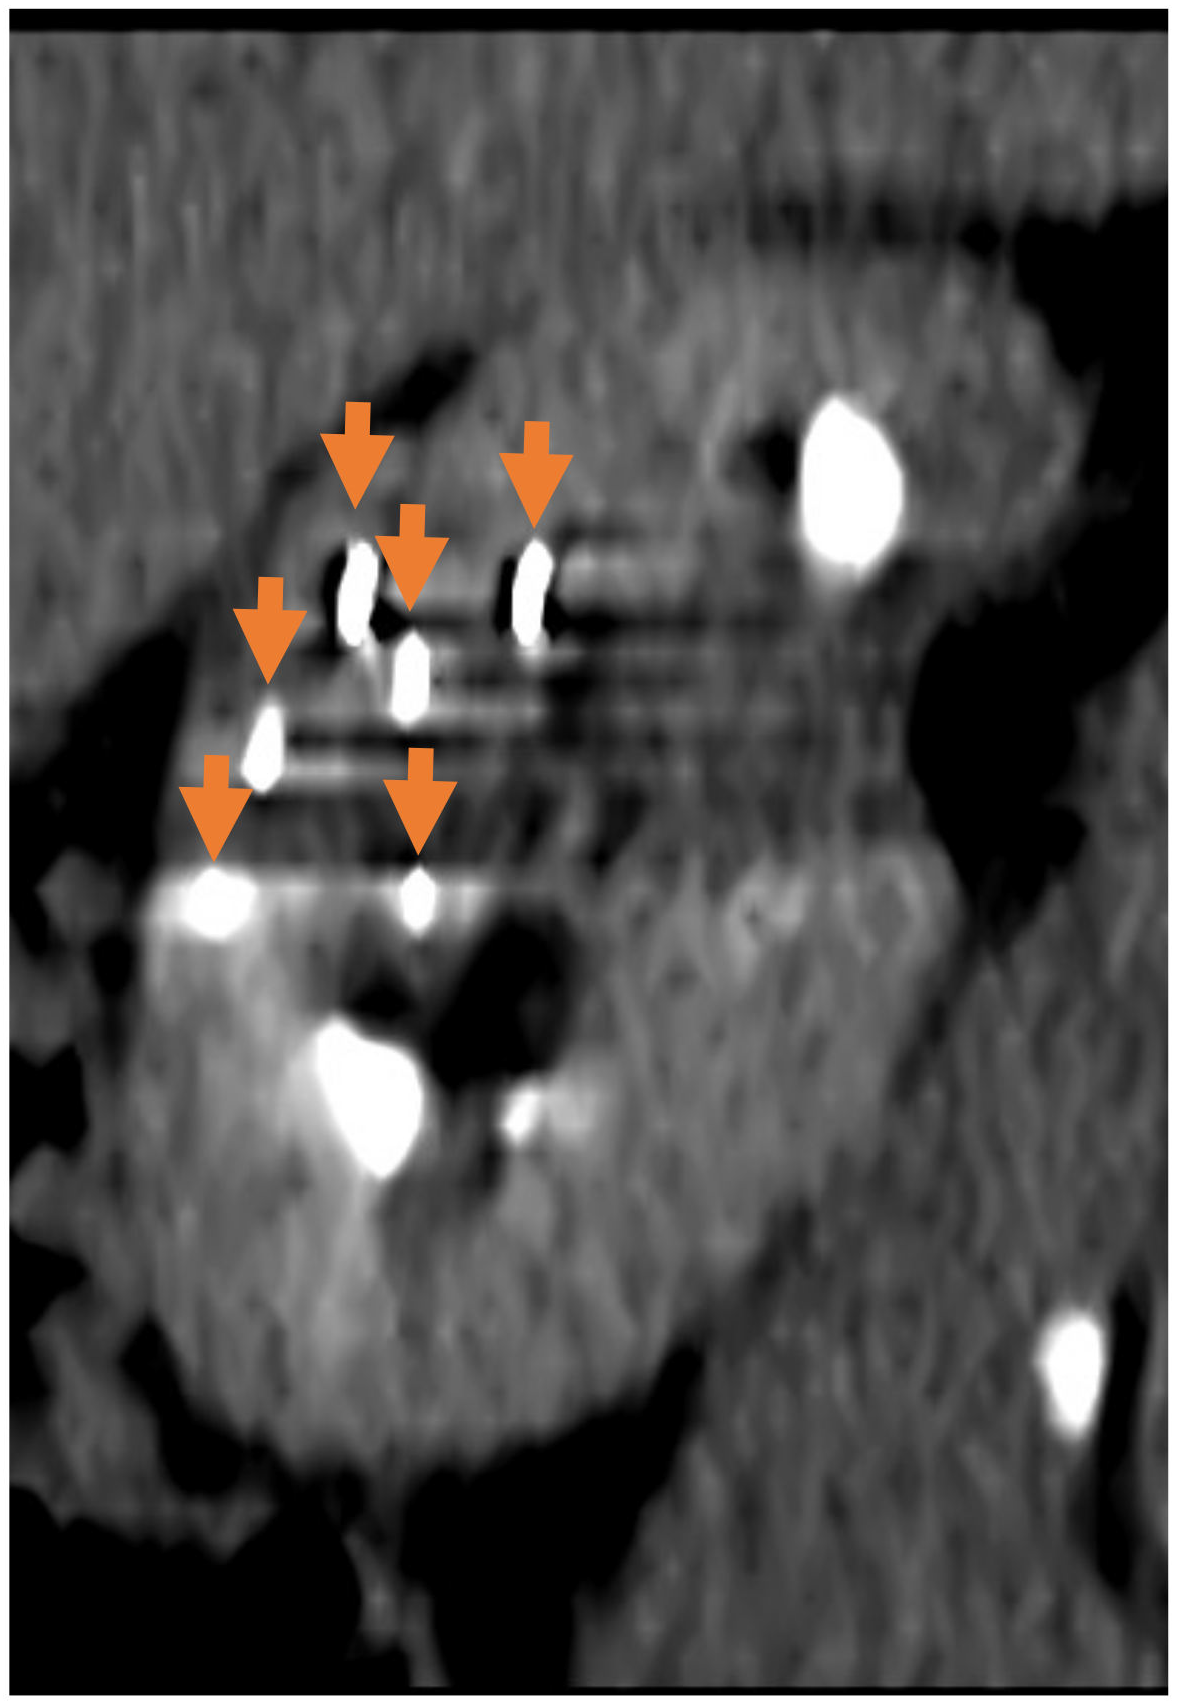

- Weiss, J.; Garnon, J.; Cazzato, R.L.; Auloge, P.; Caudrelier, J.; Dalili, D.; Boatta, E.; De Marini, P.; Koch, G.; Gangi, A. Percutaneous hydrodissection for thermoprotection during cryoablation of periureteric and pyeloureteric junction renal cell carcinomas. Abdom. Radiol. 2021, 46, 1179–1187. [Google Scholar] [CrossRef]